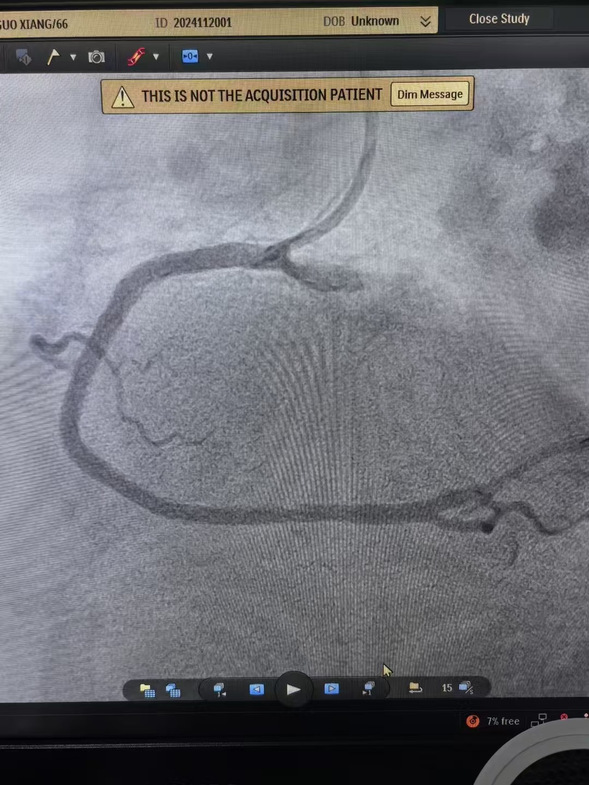

早7点,患者经120迅速到达我院大门,此时患者面色苍白、出汗明显、疼痛难止。我院医务人员立即通过绿色通道绕行急诊和病房,以最快速度将患者转移到介入手术室。在规范执行胸痛中心双绕流程基础上,心血管内四科主任沈彦祥带领医生孙智睿经临时起搏、血栓抽吸,患者胸痛症状得以缓解,状态良好。

术前、术中、术后影像

当前国际标准的门球时间是90分钟内,我院心血管内四科仅用29分钟就成功挽救了患者生命,还给患者一个完整的家。我院心血管内科专家温馨提醒:请牢记两个“120”心梗时刻能救命!——“有胸痛,我要拨打120”、“心梗救治,争取黄金时间120分”。